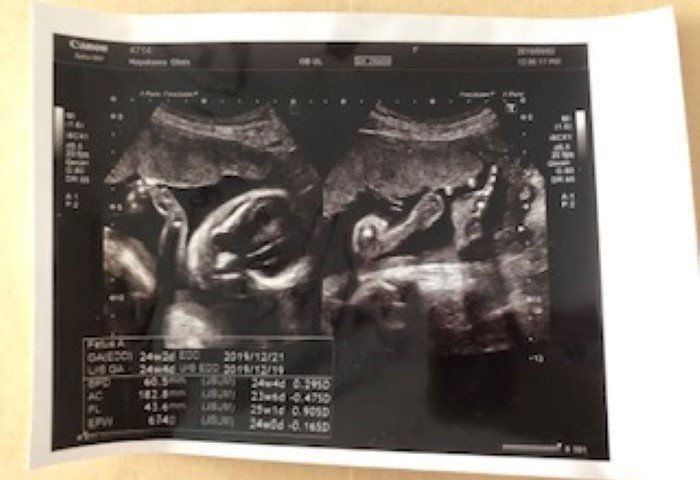

第24週 エコー写真に目線がピッタリ

24w2d

妊娠24週目の健診時、赤ちゃんがバッチリとこちらに向いている時のエコー写真です。エコー検査で見た赤ちゃんは、顔を左右に動かしたり、手足をバタバタと器用に動かしたりと、子宮内の環境にすっかり馴染んでいるように私には見えました。左の写真はパンチをした瞬間です。エコー検査の間も何回か胎動を感じていました。